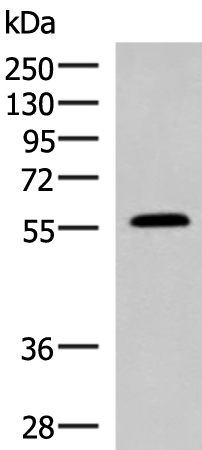

分类: 科研抗体货号: P10185别名: PROLIDASE应用: WB,IHC反应种属: Human, Mouse, Rat